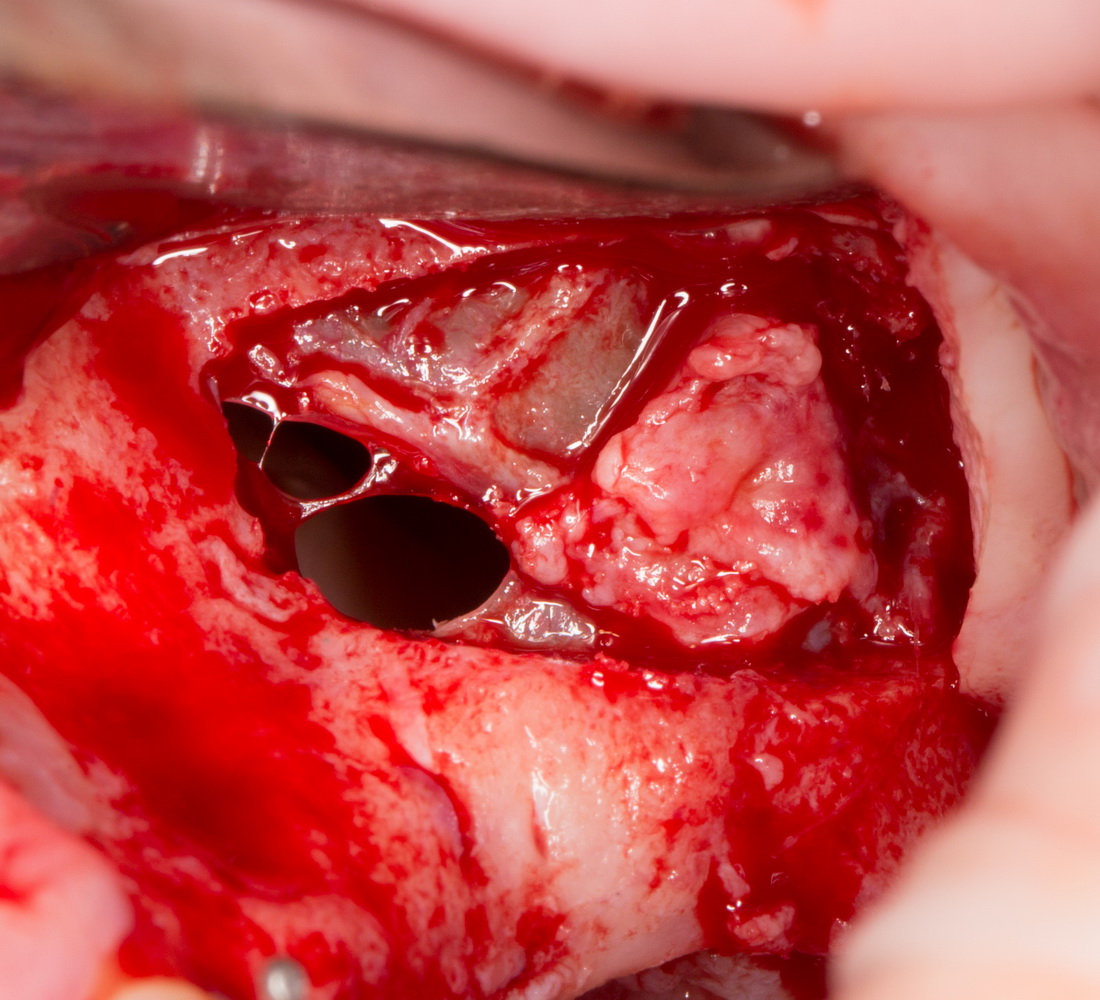

Дефект кости мы устраняем с помощью небольшого аутокостного фрагмента, который легко фиксируем двумя винтами. А пространство между ними заполняем смесью аутокостной стружки и материала Bio-Oss в пропорции 30/70:

10